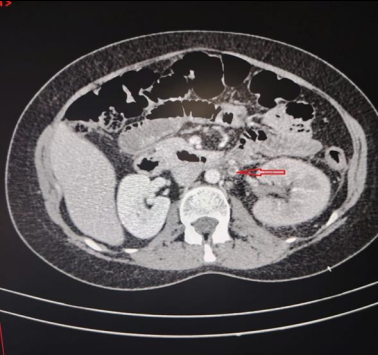

Laboratory exams revealed elevated white blood cell (WBC) count (12000 cells/mm3) with neutrophilia and (20-25 WBC in high power field) in urine examination. Other inflammatory markers like c-reactive protein (CRP) and erythrocyte sedimentation rate were also high. The initial differential diagnosis was cystitis or pyelonephritis. Abdominal ultrasound showed an enlarged left kidney, no hydronephrosis and no stones. A urine sample was sent for culture and sensitivity. The patient was admitted, and antibiotics and painkillers were initiated. An abdominal and pelvic computed tomography (CT) scan was arranged to be done the next day. CT scan with contrast showed left OVT (Figure 1, Figure 2) extending to the left renal vein (Figure 3) and inferior vena cava. Thus, she was started on anticoagulants. Urine culture was positive for Escherichia coli (ESPLs). She received low molecular weight heparin (LMWH) and shifted to warfarin. The patient was discharged home after 1 week on warfarin & oral antibiotics. A follow-up CT scan after 3 months, revealed the resolution of the clot.

Figure 1: Contrast-enhanced CT scan shows left ovarian vein with filling defect & ring enhancement indicating the thrombus (red arrow).